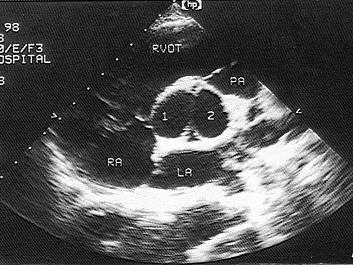

该病例最可能的诊断?(?)A.主动脉二叶瓣B.主动脉单瓣C.主动脉四叶瓣D.主动脉三叶瓣E.主动脉五叶瓣

问题 该病例最可能的诊断?(?)

选项 A.主动脉二叶瓣 B.主动脉单瓣 C.主动脉四叶瓣 D.主动脉三叶瓣 E.主动脉五叶瓣

答案 A